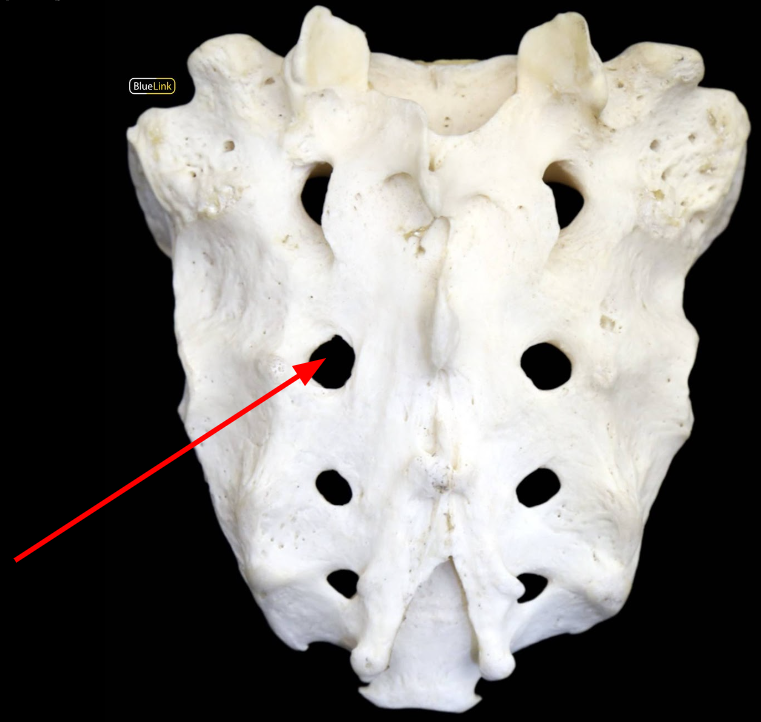

Anterior Sacral Foramen

Sacral Foramen